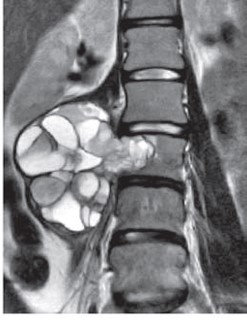

動脈瘤様骨嚢腫

• CT

• T1WI